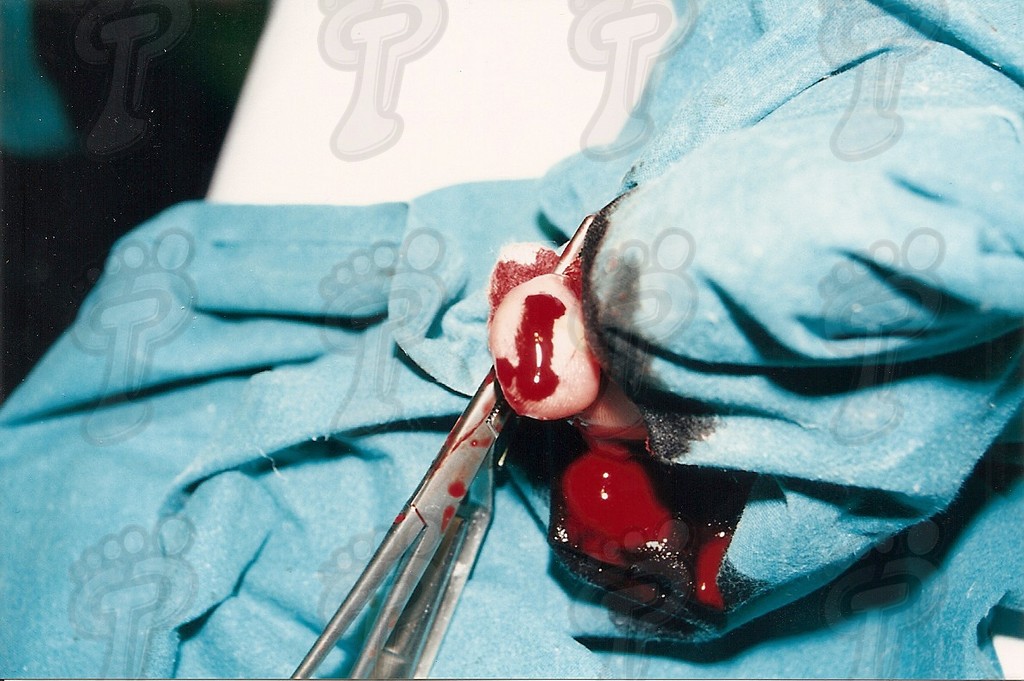

Se realiza la técnica mediante anestesia troncular y sin hemostasia (o al menos, tras el legrado). Hacemos una incisión transversal en la zona dorsoplantar distal a dos o tres milímetros de la prominencia ósea, se introduce el bisturí perpendicularmente al eje de la falange hasta tocar hueso, y a partir de ahí, se desciende bien próximo al tejido ósea para separar partes blandas y delimitar la exóstosis. No se debe incidir lateralmente porque podríamos dañar el paquete neurovascular. Se introduce un cincel separando tejido óseo blando y se delimita la prominencia ósea, la cual suele ser mayor que en la radiografía debido a una zona cartilaginosa radiotransparente. Se legra exhaustivamente con la lima de proximal a distal y de profundidad a superficie (sin vaivén). En las primeras capas (cortical y periostio) notamos que la lima patina y a continuación percibimos el raspado óseo. Con el pulgar de la mano pasiva presionamos de proximal a distal para que salgan al exterior las partículas óseas legradas. Legramos ampliamente ya que al producir un traumatismo óseo siempre hay una regeneración ósea debida a la rica red capilar superficial. Si no lo hacemos así, se puede volver a regenerar el tejido óseo produciendo de nuevo y en poco tiempo la exóstosis. Favorecemos el sangrado de la zona para ayudar a eliminar posibles partículas óseas. Lavamos abundantemente la incisión con suero fisiológico. Volvemos a realizar otra radiografía dorsoplantar intraquirúrgica, a ser posible en la misma posición pre-quirúrgica (la radiografía oblícua no da imagen real del tamaño de exóstosis y la lateral no muestra nada). Hemos de observar en la radiografía que la cabeza de la falange proximal está en el mismo plano que la base de la falange media, ya que si no puede producir algias post-operatorias. Si observamos una nebulosa en la radiografía, son pequeñas partículas o fragmentos óseos que deben drenarse mediante lavados ya que si no se reagrupan y vuelven a regenerar la exóstosis de nuevo. Se han de hacer lavados y radiografías hasta quedar la zona totalmente limpia de fragmentos óseos. Infiltramos anestésico y corticoides en proporción 9 a 1. No hemos de abusar del corticoide porque al entrar en contacto con la trabécula ósea que hemos dejado como capa externa, puede producir problemas graves post-operatorios, tales como la osteoporosis. Se aconseja primero cargar el corticoide y luego el anestésico para evitar que se cristalice el corticoide produciendo trastornos yatrogénicos. Una vez infiltrada la mezcla, presionamos la herida proximal a distal para drenarla ya que sólo nos interesa el efecto farmacológico antiinflamatorio. A continuación, suturamos con seda 5/0 mediante dos puntos simples. En el caso que os mostramos ferulizamos el quinto dedo con una gasa de “U”, impidiendo así la movilización dorsoplantar y, para más sujeción, se une al cuarto dedo con la ayuda de un vendaje circular. Puede impregnarse en yodo la férula en forma de “U” para darle mayor rigidez o consistencia y por lo tanto, menor movilidad al quinto dedo. El vendaje debe ser semicompresivo alineado el dedo. Aconsejamos al paciente reposo durante 48 horas. Pautamos la analgesia correspondiente, y le informamos de las actuaciones que debe efectuar ante determinadas anomalías. Retiramos el apósito quirúrgico a las 48 horas y se cura con povidona yodada dos veces al día (mañana y tarde). Enseñamos al paciente a hacer el vendaje en forma de “U”. A los siete días retiramos la sutura y confeccionamos una cresta de silicona, que debería emplear hasta alcanzar la normalidad articular. Dicha silicona ha de ser utilizada durante un período que oscile entre seis meses a un año.